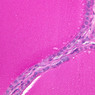

The thyroid gland (slide B-51, lead hematoxylin [10x, 20x, 40x, 40x]; B-52, H&E [10x-labeled, 20x, 40x-labeled, 40x]; B-53, PAS [2.5x, 10x, 20x, 40x]) consists of many closely packed, roughly spherical structures known as follicles, which are enclosed in a thick connective tissue capsule. Connective tissue septa extend from the capsule into the substance of the gland, carrying numerous blood vessels. Follicular cells are arranged as shells of simple cuboidal epithelium surrounding a gelatinous mass known as colloid. Look for a ring of epithelial cells around the homogeneous, pink-staining colloid. The cytoplasm of the follicular cells (principal cells) is faintly basophilic. The follicular cells secrete thyroglobulin, a glycoprotein, which is stored extracellularly in the colloid. In response to TSH, the follicular cells endocytose the colloid and hydrolyze it to form thyroxine. You can see where colloid has been resorbed because this process leaves small holes in the colloid adjacent to the follicular cells. These holes are known as resorption lacunae (B-52 [10x, 20x, 40xlabeled]). Very active follicles may exhibit a columnar epithelium and increased numbers of resorption lacunae. Between follicles, the stroma of the thyroid gland consists of a thin layer of connective tissue and a rich capillary network. Parafollicular cells (light cells or C cells) are located in the connective tissue between follicles or adjacent to follicular cells within follicles. When they lie within the follicular wall, the parafollicular cells do not reach the lumen. Parafollicular cells are slightly larger than the follicular cells and, in H & E preparations, have a more lightly stained cytoplasm (B-52, H&E [10x, 20x, 40x-labeled] [10x-labeled, 20x, 40x-labeled] [10x, 20x, 40x] [10x, 20x, 40x]; B-53, PAS [10x, 20x, 40x]). Parafollicular cells are readily identifiable in slide B-51 (stained with lead hematoxylin), where they appear as purplish-black structures in which the nuclei are difficult to discern (B-51 [10x, 20x, 40x-labeled]). These cells secrete calcitonin, which lowers serum calcium levels by inhibiting bone resorption and accelerating osteoid calcification.